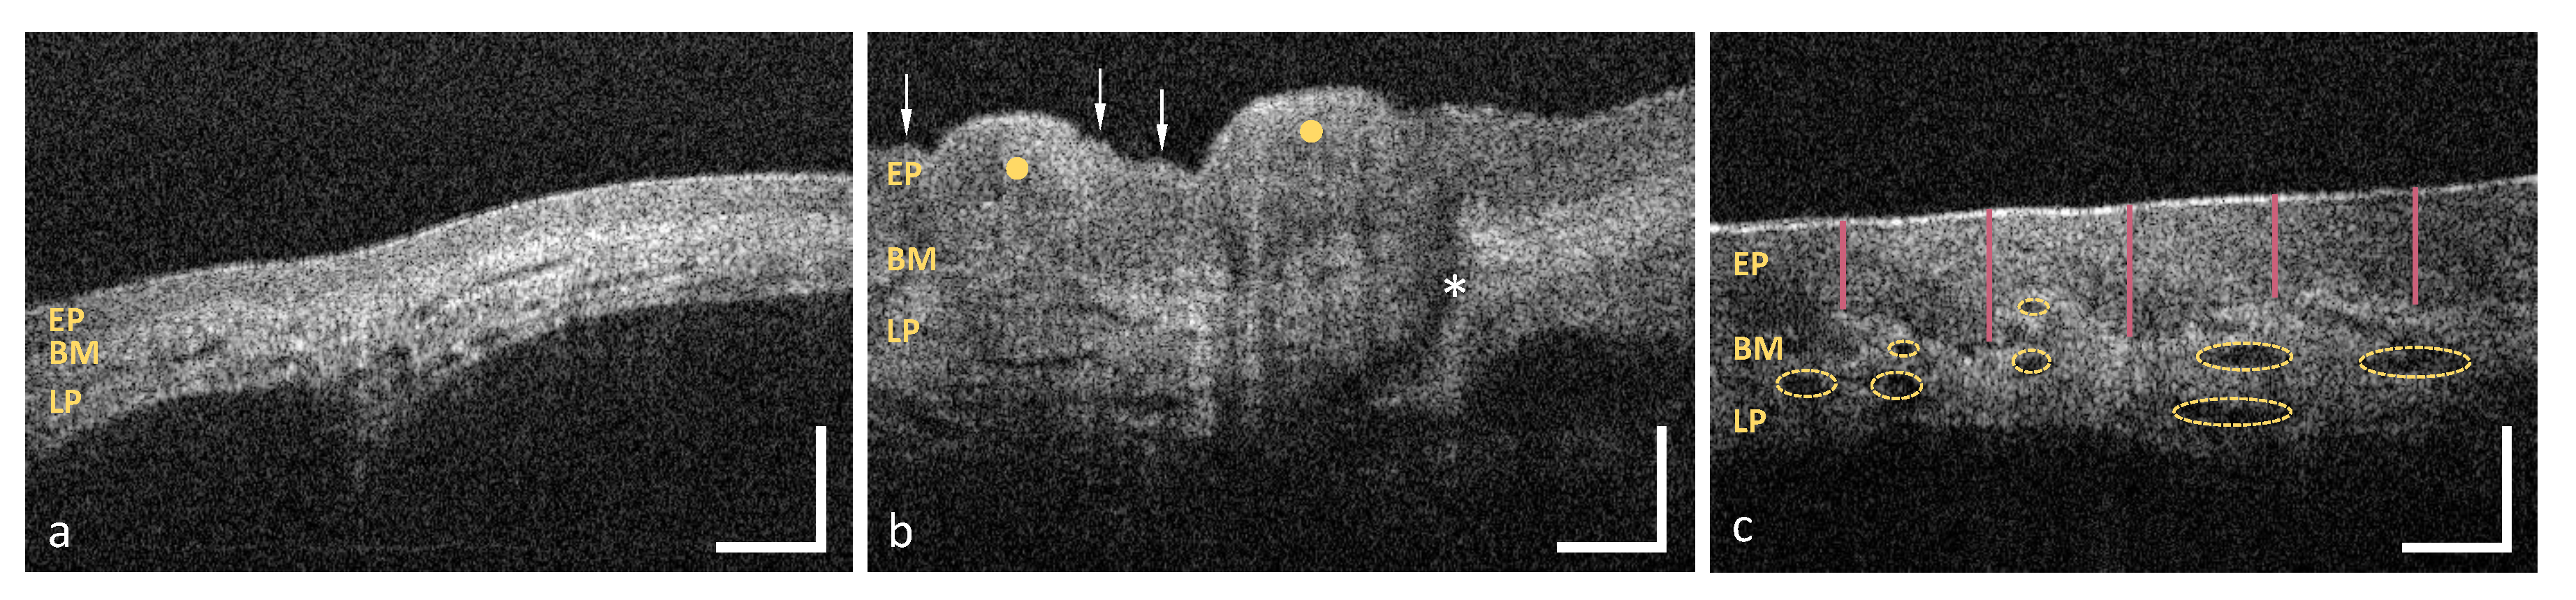

3.1. Labial and Alveolar Mucosa

3.2. Buccal Mucosa

3.3. Sublingual Mucosa

3.4. Hard Palate

3.5. Soft Palate and Oropharynx

3.6. Palatine Tonsils